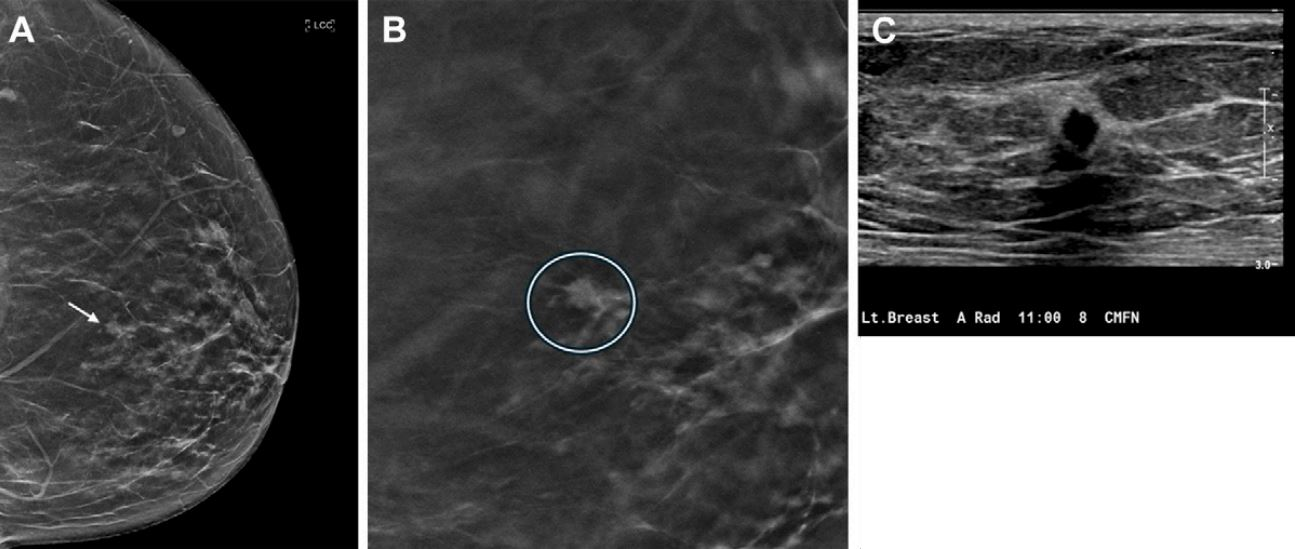

Reliable evidence about the long-term impact of digital breast tomosynthesis is in relatively short supply, so the publication of a study from the U.S. is bound to generate great interest.